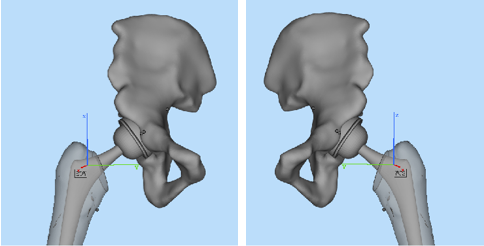

李寬新主任接診后詳細(xì)詢(xún)問(wèn)病史、體格檢查(圖一),結(jié)合患者術(shù)前骨盆平片,骨盆CT(圖二、三)平掃三維重建,診斷為:“雙側(cè)股骨頭壞死繼發(fā)終末期骨關(guān)節(jié)炎(Ficat IV期)”。為實(shí)行快速康復(fù),精準(zhǔn)解剖重建髖關(guān)節(jié),提出應(yīng)用微創(chuàng)OCM入路聯(lián)合Harris窩技術(shù),實(shí)現(xiàn)微創(chuàng)和精準(zhǔn)全髖關(guān)節(jié)置換的治療方案。

針對(duì)周先生的情況,李寬新主任、張衡博士在手術(shù)前進(jìn)行了詳細(xì)完備的術(shù)前設(shè)計(jì)(圖四),并在3Dbody、Mimics、Magic軟件上進(jìn)行入路設(shè)計(jì)和模擬手術(shù)(圖五、六),計(jì)算出髖臼杯和股骨柄大小及髖臼杯外展角、前傾角、旋轉(zhuǎn)中心位置等關(guān)鍵指標(biāo)。6月16日在周建生教授的指導(dǎo)支持下,由李寬新主任、張衡博士在我院成功應(yīng)用微創(chuàng)OCM入路聯(lián)合Harris窩技術(shù)為患者實(shí)施一期雙側(cè)人工全髖關(guān)節(jié)置換術(shù)。手術(shù)切口僅7cm,術(shù)中出血量約80ml。(圖七)